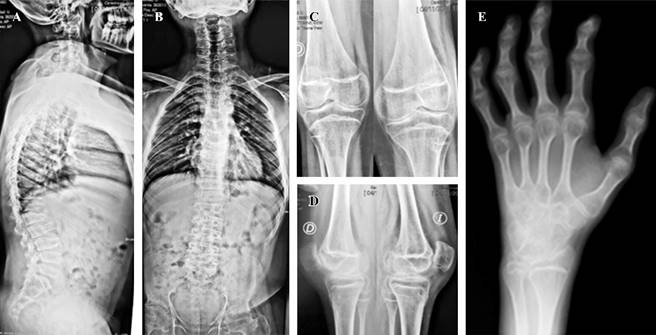

Radiográficamente presentaba coxartrosis bilateral, con pobre calidad ósea y un fémur proximal tipo Dorr C (Figura 1). Además, presentaba camptodactilia, platispondilia, discopatías, disminución de la luz articular y ensanchamiento episario en ambas rodillas (Figura 2). El análisis de laboratorio no presentaba alteraciones en marcadores inflamatorios, ni ningún otro tipo de alteración.

Figura 2: A y B) Espinograma completo anteroposterior y lateral, en el que se observa la platispondilia, la disminución de la altura de los discos intervertebrales y el torso corto. C y D) Radiografías anteroposterior y lateral de ambas rodillas; muestran la disminución de la luz articular, el ensanchamiento epifisario y la pobre calidad ósea. E) Radiografía oblicua de mano; se observa la camptodactilia.